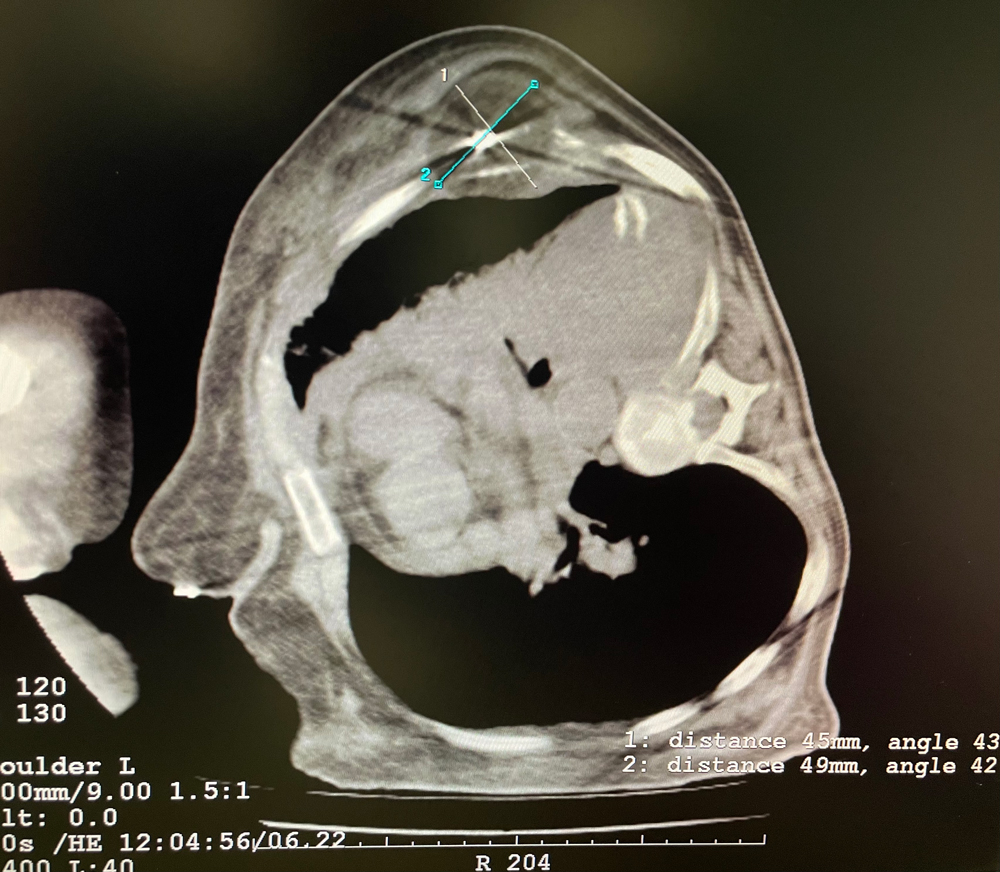

患者一

女,56歲,肺轉移瘤,骶骨、左側肋骨各一轉移灶,病灶大小均為5cm。骶骨轉移灶、肋骨轉移灶各進行2個凍融循環。患者術后狀況良好。